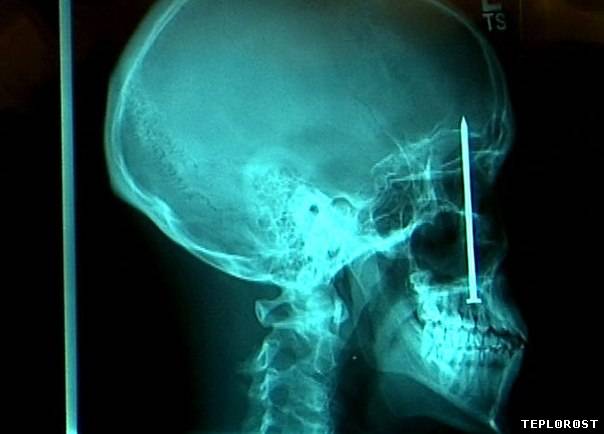

Мужчина случайно выстрелил себе в череп гвоздем из строительного пистолета.

Гвозди в черепе человека.